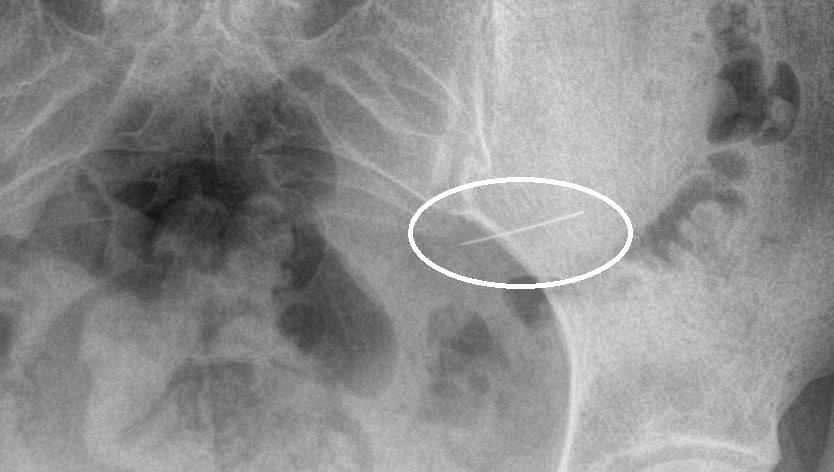

Жительница Красногорска случайно проглотила швейную иглу.

Жительница Красногорска случайно проглотила швейную иглу — она сразу обратилась за медицинской помощью, что позволило избежать серьезных осложнений, сообщает Минздрав Подмосковья.

Детали произошедшего не уточняются. К моменту поступления в больницу игла была в желудке. Опасный предмет был благополучно удален с помощью эндоскопического оборудования. «Если бы игла задержалась в организме на более долгий срок, это могло бы повлечь за собой серьезные осложнения, такие как перфорация стенок желудка или кишечника, кровотечение, перитонит и даже сепсис», — сказал заведующий первым хирургическим отделением Николай Мурашов.